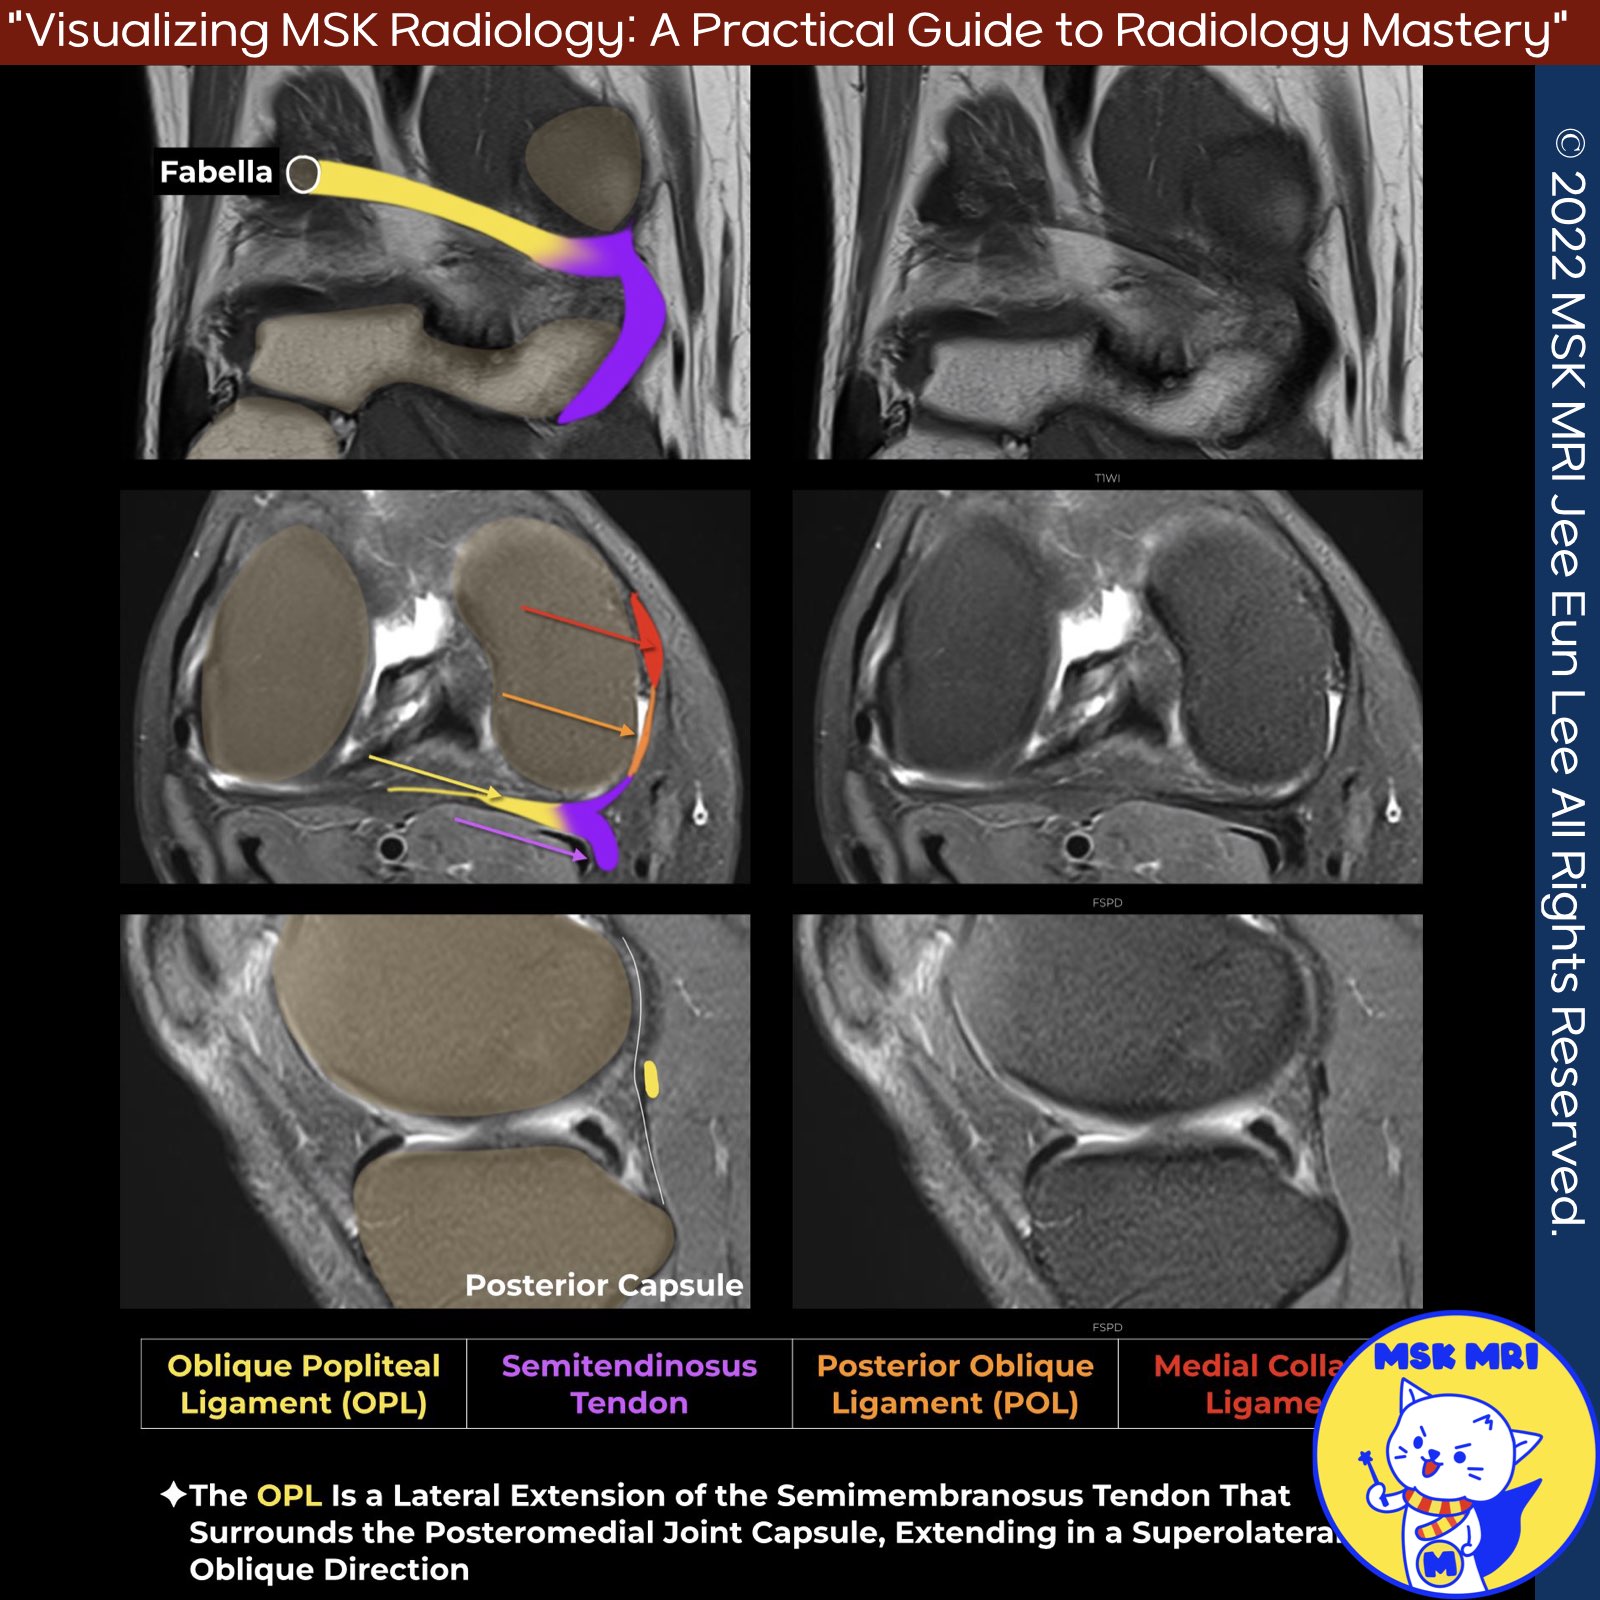

📌Oblique Popliteal Ligament

- A broad component extends into the OPL, which courses along the posterior capsule of the knee.

- Laterally, the OPL attaches to the fabella, meniscofemoral portion of the posterolateral joint capsule, and plantaris muscle.

- On coronal imaging, the OPL appears as an obliquely oriented thick band.

- While sometimes thin, a thickened OPL can be seen extending obliquely from the semimembranosus tendon toward the lateral femoral condyle.

✅ Capsular arm of Posterior Oblique Ligament

- The superior/capsular arm of the POL is mainly superior to the joint line and continuous with the posterior joint capsule.

- It merges with the capsular arm of the semimembranosus tendon to form the proximal OPL.

✅ Extension to the OPL of Semimembranosus tendon expansion

- Forms a tendinous expansion towards the OPL, running along the posterior capsule of the knee about 2 cm above the joint line.